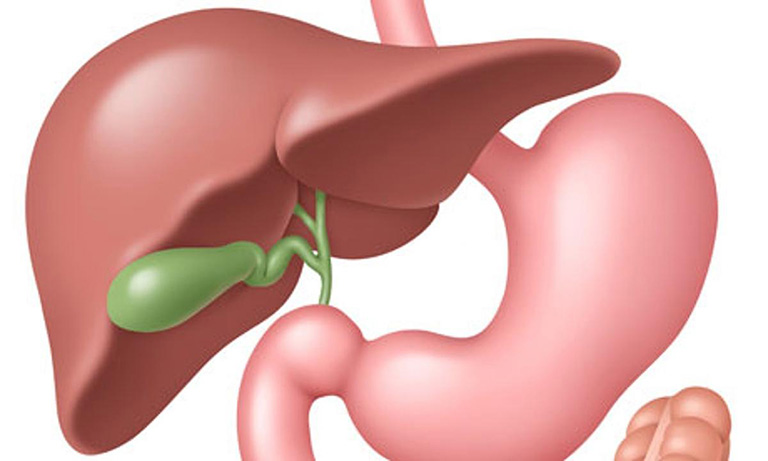

Vì sao cần phòng ngừa bệnh sỏi mật?

Không phải ai mắc sỏi mật cũng có triệu chứng rõ ràng, nhưng một khi sỏi gây tắc nghẽn đường mật hoặc viêm túi mật cấp, tình trạng có thể trở nên nguy hiểm. Nhiều bệnh nhân buộc phải sử dụng biện pháp can thiệp như nội soi, thậm chí phẫu thuật cắt túi mật để tránh biến chứng.

Nguyên nhân chính gây sỏi mật

Để xây dựng chiến lược phòng ngừa bệnh sỏi mật hiệu quả, người bệnh cần hiểu những yếu tố dẫn đến sự kết tụ của dịch mật tạo thành sỏi.

Dưới đây là những nguyên nhân thường gặp:

- Chế độ ăn nhiều chất béo, ít chất xơ khiến nồng độ cholesterol trong dịch mật tăng cao

- Túi mật co bóp yếu, làm dịch mật ứ đọng

- Nhiễm trùng đường mật, tạo điều kiện hình thành sỏi sắc tố

- Rối loạn nội tiết, nhất là ở phụ nữ mang thai hoặc dùng hormone

- Béo phì, tiểu đường hoặc bệnh gan mạn tính

Việc xác định đúng nguyên nhân giúp người bệnh điều chỉnh lối sống phù hợp để giảm nguy cơ phát triển sỏi.